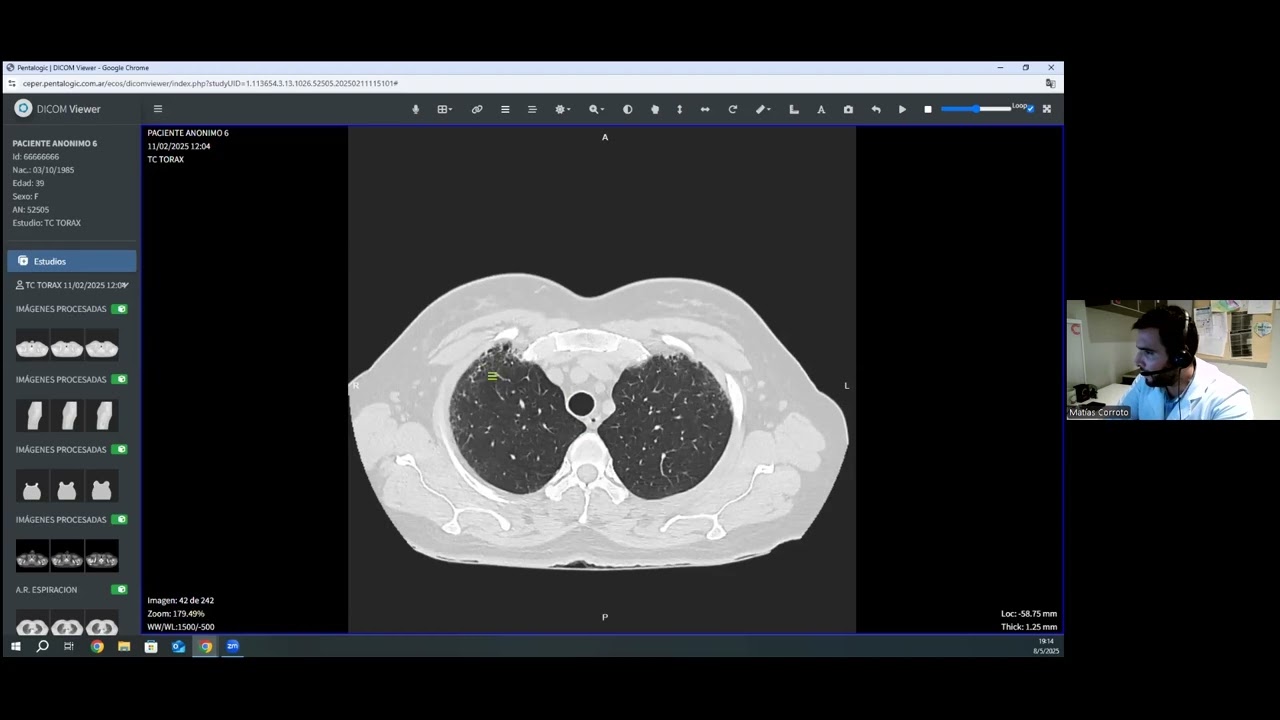

Como lo Hago -Valoración de Resecabilidad Quirúrgica en el Diagnóstico Inicial de Cáncer de Páncreas

Disertante: Dr. Juan Carlos Spina

Coordinadora: Dra. Celina Capiel